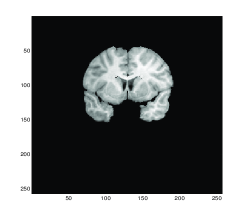

The values of the quantitative measurements for Test 2 are recorded in Table 2 where the lowest values of ε𝜀\varepsilon are given by the Gaussian curvature model indicating higher similarity between the transformed template result and the reference image. However, our proposed model required more time than the other models since the model consists more variables than the others.

A brief summary. The linear curvature model is relatively easy to solve, based on approximation of the mean curvature. The mean curvature model for image registration is highly nonlinear, making it challenging to solve. The Gaussian curvature resembles the mean curvature in many ways, though different, but its model appears to deliver better quality than the mean curvature. The diffeormorphic demon model is equivalent to the second order gradient descent on the SSD as shown in [17]. The model is only limited to mono-modality images and it is not yet applicable to multi-modality images. Our Gaussian curvature model however can be easily modified to work with multi-modality images by replacing the SSD by a mutual information or normalised gradient fields based regularizer; an optimal solver is yet to be developed. We show one example of extension to a pair of multi-modality images in Fig.5.